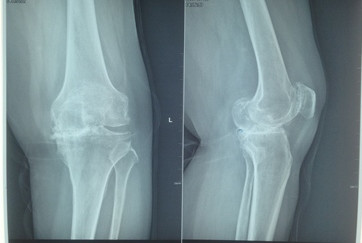

患者曾在2015年因右膝关节重度骨性关节炎,在西安行右全膝关节置换术。住入我院后,骨二科副主任医师胡洪波为患者做了详细全面的检查,最终诊断为左膝关节骨性关节炎IV期,右全膝关节置换术后,高血压病3级。因为患者左膝关节的疼痛,导致走路不稳,影响到了日常生活,已经达到了手术指征,骨二科医师在经过和患者及家属的反复沟通后,决定为患者实施左侧全膝关节表面置换术。

10月15日,由胡洪波主刀,为患者施左膝关节骨性关节炎全膝关节表面置换术,手术过程顺利。术后2天患者开始屈膝运动训练及肌力训练,3天即可扶支柱下床行走,术后7天出院,术中患者的膝关节畸形也成功纠正,目前患者膝关节功能良好,行动无阻碍。